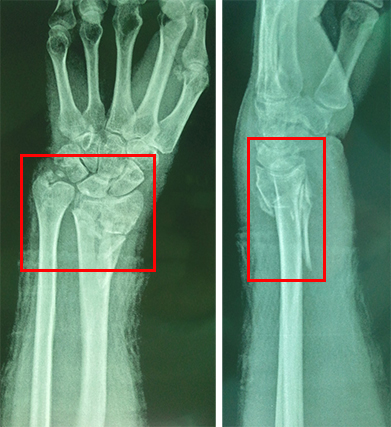

患者,女,70岁,跌倒致左腕肿痛畸形2小时入院既往高血压、心衰病史,长期服用呋塞米,地高辛等,外伤前1周自行停药,查体:BP180/100mmHg,左尺桡骨远端肿胀,餐叉样畸形,压痛,可及骨擦音,活动受限,左上肢末梢血运可,感觉下降。X线提示:

四周后复查X线提示: